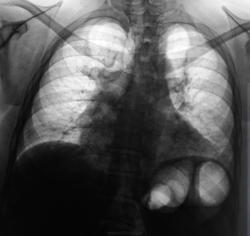

Пациентка взята на контроль после флюорографии...

Дела сердечные, грудинный (или как его там?) горб.

А на лимфому не похоже?

а почему Вы решили что здесь лимфома? И что можно сказать про л\узел в правом корне?

Я вовсе не решил, что "это" лимфома, я, просто, в сомнениях, вот, и решил узнать мнения коллег.